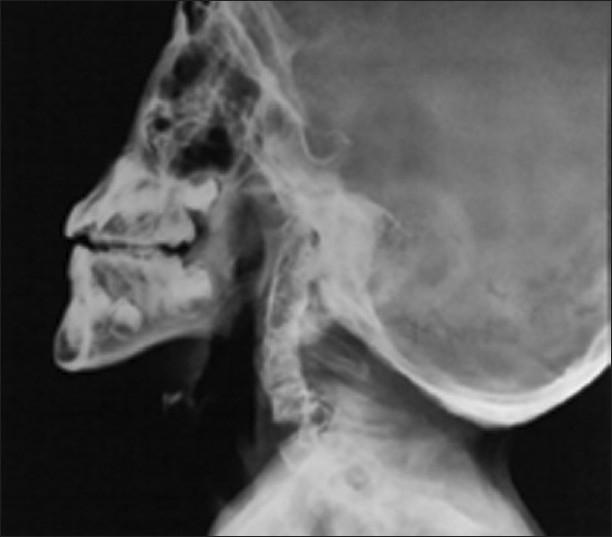

Noonan syndrome is a genetically transmitted autosomal dominant disorder characterized by various anatomic anomalies and pathophysiologic derangements. Anesthetic management in such cases poses a multitude of challenges, especially related to the airway management and maintenance of cardiovascular stability. We report a case of a 9-year-old male child weighing 24 kg, who was diagnosed as a case of Noonan syndrome and had undergone ligation of patent ductus arteriosus during early childhood. The child was operated on for release of bilateral neck bands under general anesthesia. The case report pertains to the successful airway and anesthetic management in the background of difficult airway and existence of various cardiac lesions.

努南综合征是一种常染色体显性遗传疾病,其特征为各种解剖学异常和病理生理紊乱。此类病例的麻醉管理面临诸多挑战,尤其是在气道管理和维持心血管稳定性方面。我们报告一例9岁男性患儿,体重24千克,被诊断为努南综合征,幼儿期曾接受动脉导管未闭结扎术。该患儿在全身麻醉下接受双侧颈部束带松解手术。本病例报告涉及在困难气道和存在多种心脏病变背景下成功的气道和麻醉管理。